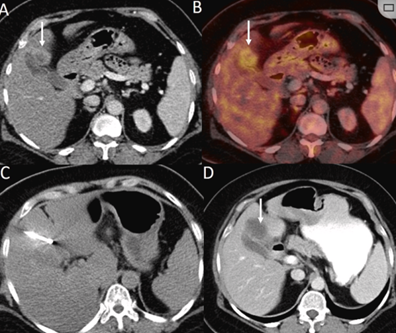

CT引導(dǎo)的冷凍消融

(a) 射頻消融后在病變邊緣顯示殘余增強(qiáng)。(b) 冷凍消融術(shù)中影像顯示冰球完全覆蓋病變。(c) 19個(gè)月后隨訪,沒有發(fā)生局部腫瘤進(jìn)展。完全消融率為97%(66/68);2名患者均接受了額外的冷凍消融,隨后實(shí)現(xiàn)完全消融。平均隨訪期為 12.8 個(gè)月(范圍:3-27 個(gè)月)。所有患者均接受影像復(fù)查(CT 或 MRI)。11個(gè)病灶(16.2%)檢測(cè)到局部腫瘤進(jìn)展,6、12和18個(gè)月時(shí)的累積局部腫瘤進(jìn)展率分別為4%、8.2%和20.5%。8例出現(xiàn)遠(yuǎn)處肝內(nèi)或肝外病變的患者接受經(jīng)動(dòng)脈化療栓塞、經(jīng)動(dòng)脈化療栓塞加射頻消融治療或全身化療。

79 歲男性,肝轉(zhuǎn)移(結(jié)直腸癌)腫瘤的完全消融病例

( a ) 軸向 MRI 和 ( b ) 軸向 CT 顯示肝S8段有一個(gè)16mm的病灶,鄰近肝緣。( c )冷凍消融期間CT顯示放置了2個(gè)冷凍探針,低密度冰球包圍病灶。(d)術(shù)后1個(gè)月隨訪 CT顯示冰球?qū)?yīng)的壞死區(qū)域,未見復(fù)發(fā)。(e)術(shù)后6個(gè)月的CT,壞死區(qū)域縮小,未見復(fù)發(fā)。(f)與基線影像(g)相比,12個(gè)月后的FDG-PET/CT顯示未見FDG攝取。

62歲女性,肝轉(zhuǎn)移(卵巢癌)腫瘤的完全消融病例(a)軸向CT顯示病變位置毗鄰心臟和上腔靜脈(黑色箭頭)。(b)術(shù)中軸向CT掃描:使用三個(gè)冷凍探針。1個(gè)月后的軸向(e)和冠狀位(f)增強(qiáng)CT掃描顯示低密度區(qū)域,由于肉芽組織反應(yīng)引起的邊緣增強(qiáng)。

技術(shù)成功100%,92% 的病灶中觀察到腫瘤完全消融。16 名患者 (33%) 出現(xiàn)局部復(fù)發(fā)。10 名患者 (20%) 因局部復(fù)發(fā)或腫瘤消融不完全而接受二次冷凍消融術(shù)。